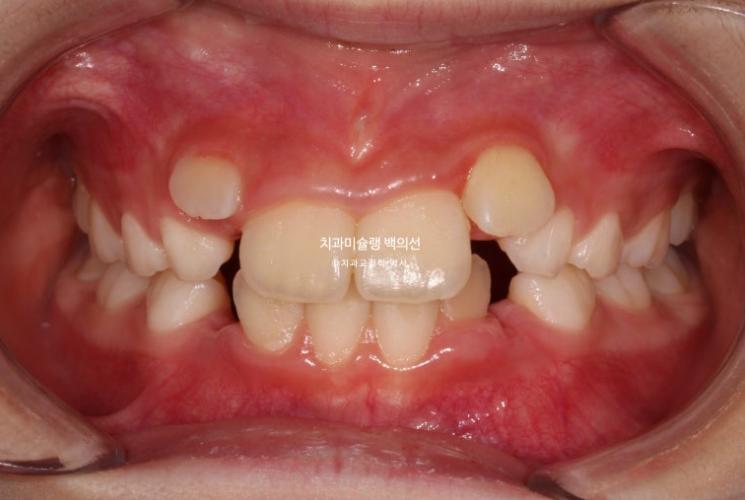

2년 전 교정치료를 위해 내원한 만 8세 어린이입니다.

이제 겨우 유치 앞니가 빠지고 영구치 앞니가 나오는 시기인데

앞니부터 심한 덧니로 내려오니 부모님이 놀라서 오셨습니다.

이 날 자리가 좁으면 치아가 회전된 상태로 나오거나 입천장으로 나오거나 이 친구처럼 덧니로 내려오게 됩니다.

23.06

아랫니도 공간이 많이 부족합니다.